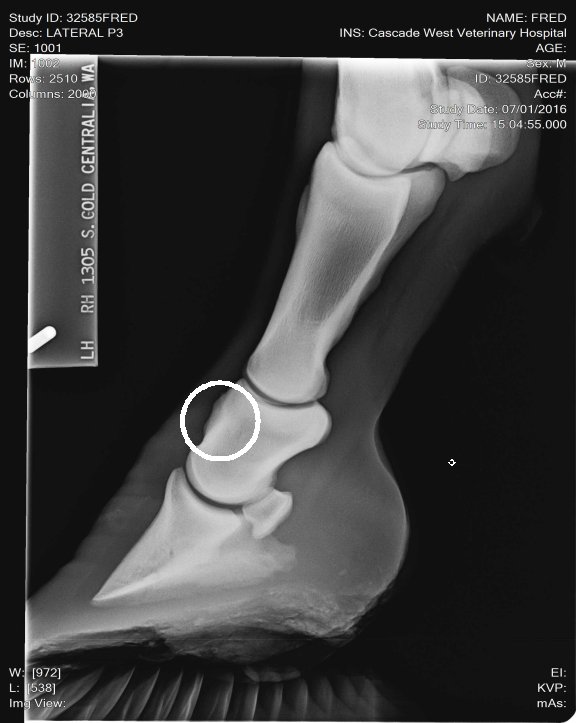

Location: Washington | So we got a young, 3 yr old, horse from some friend to break, put some time on and sale for them. AWESOME little horse with a nice cowbred pedigree. Our 7 yr old was riding him his 14th ride, he now has about 45 days on him. She's now taken over the reins working cows and trail riding. He's had a pretty easy life, no injuries or illness. We started advertising and have LOTS of interest BUT he has failed two pre purchase exams for lameness on the flex test. First was front left yesterday was front right. First vet check took X rays, he said he was clean, vet that looked at him yesterday said no, high ringbone! He rides sound but wont pass the flex tests. What are your expereinces with this? What are our options? Maintence?Β Β We WILL be up front and honest with his condition to potenial buyers but I'd like to know other peoples opinions and your most successful treatments.

I'll try this again I circled the wrong place! lol Thats what I get for doing this before coffee!

(unnamed (1)b.jpg)

(unnamedb.jpg)

Location: Lost in the swamps | My opinion these X rays don't look bad. I don't see any involvement in the joint spaces. I've seen a lot worse. He's got really long toes, you need to show your farrier these x rays and have him shorten and round his toes to quicken his break over is very important for horses dealing with ringbone. long toes create a lot of torque! This can also lead to lamine inflammation. The p-1 and p-2 is a low motion joint so it can actually fuse and the horse still have soundness. Your p2 and coffin joint is where you don't want any issues of ring bone. And I don't see any there. The upper pattern has some oddity near the seasmoid bone. Just curious did your vet mention anything? |